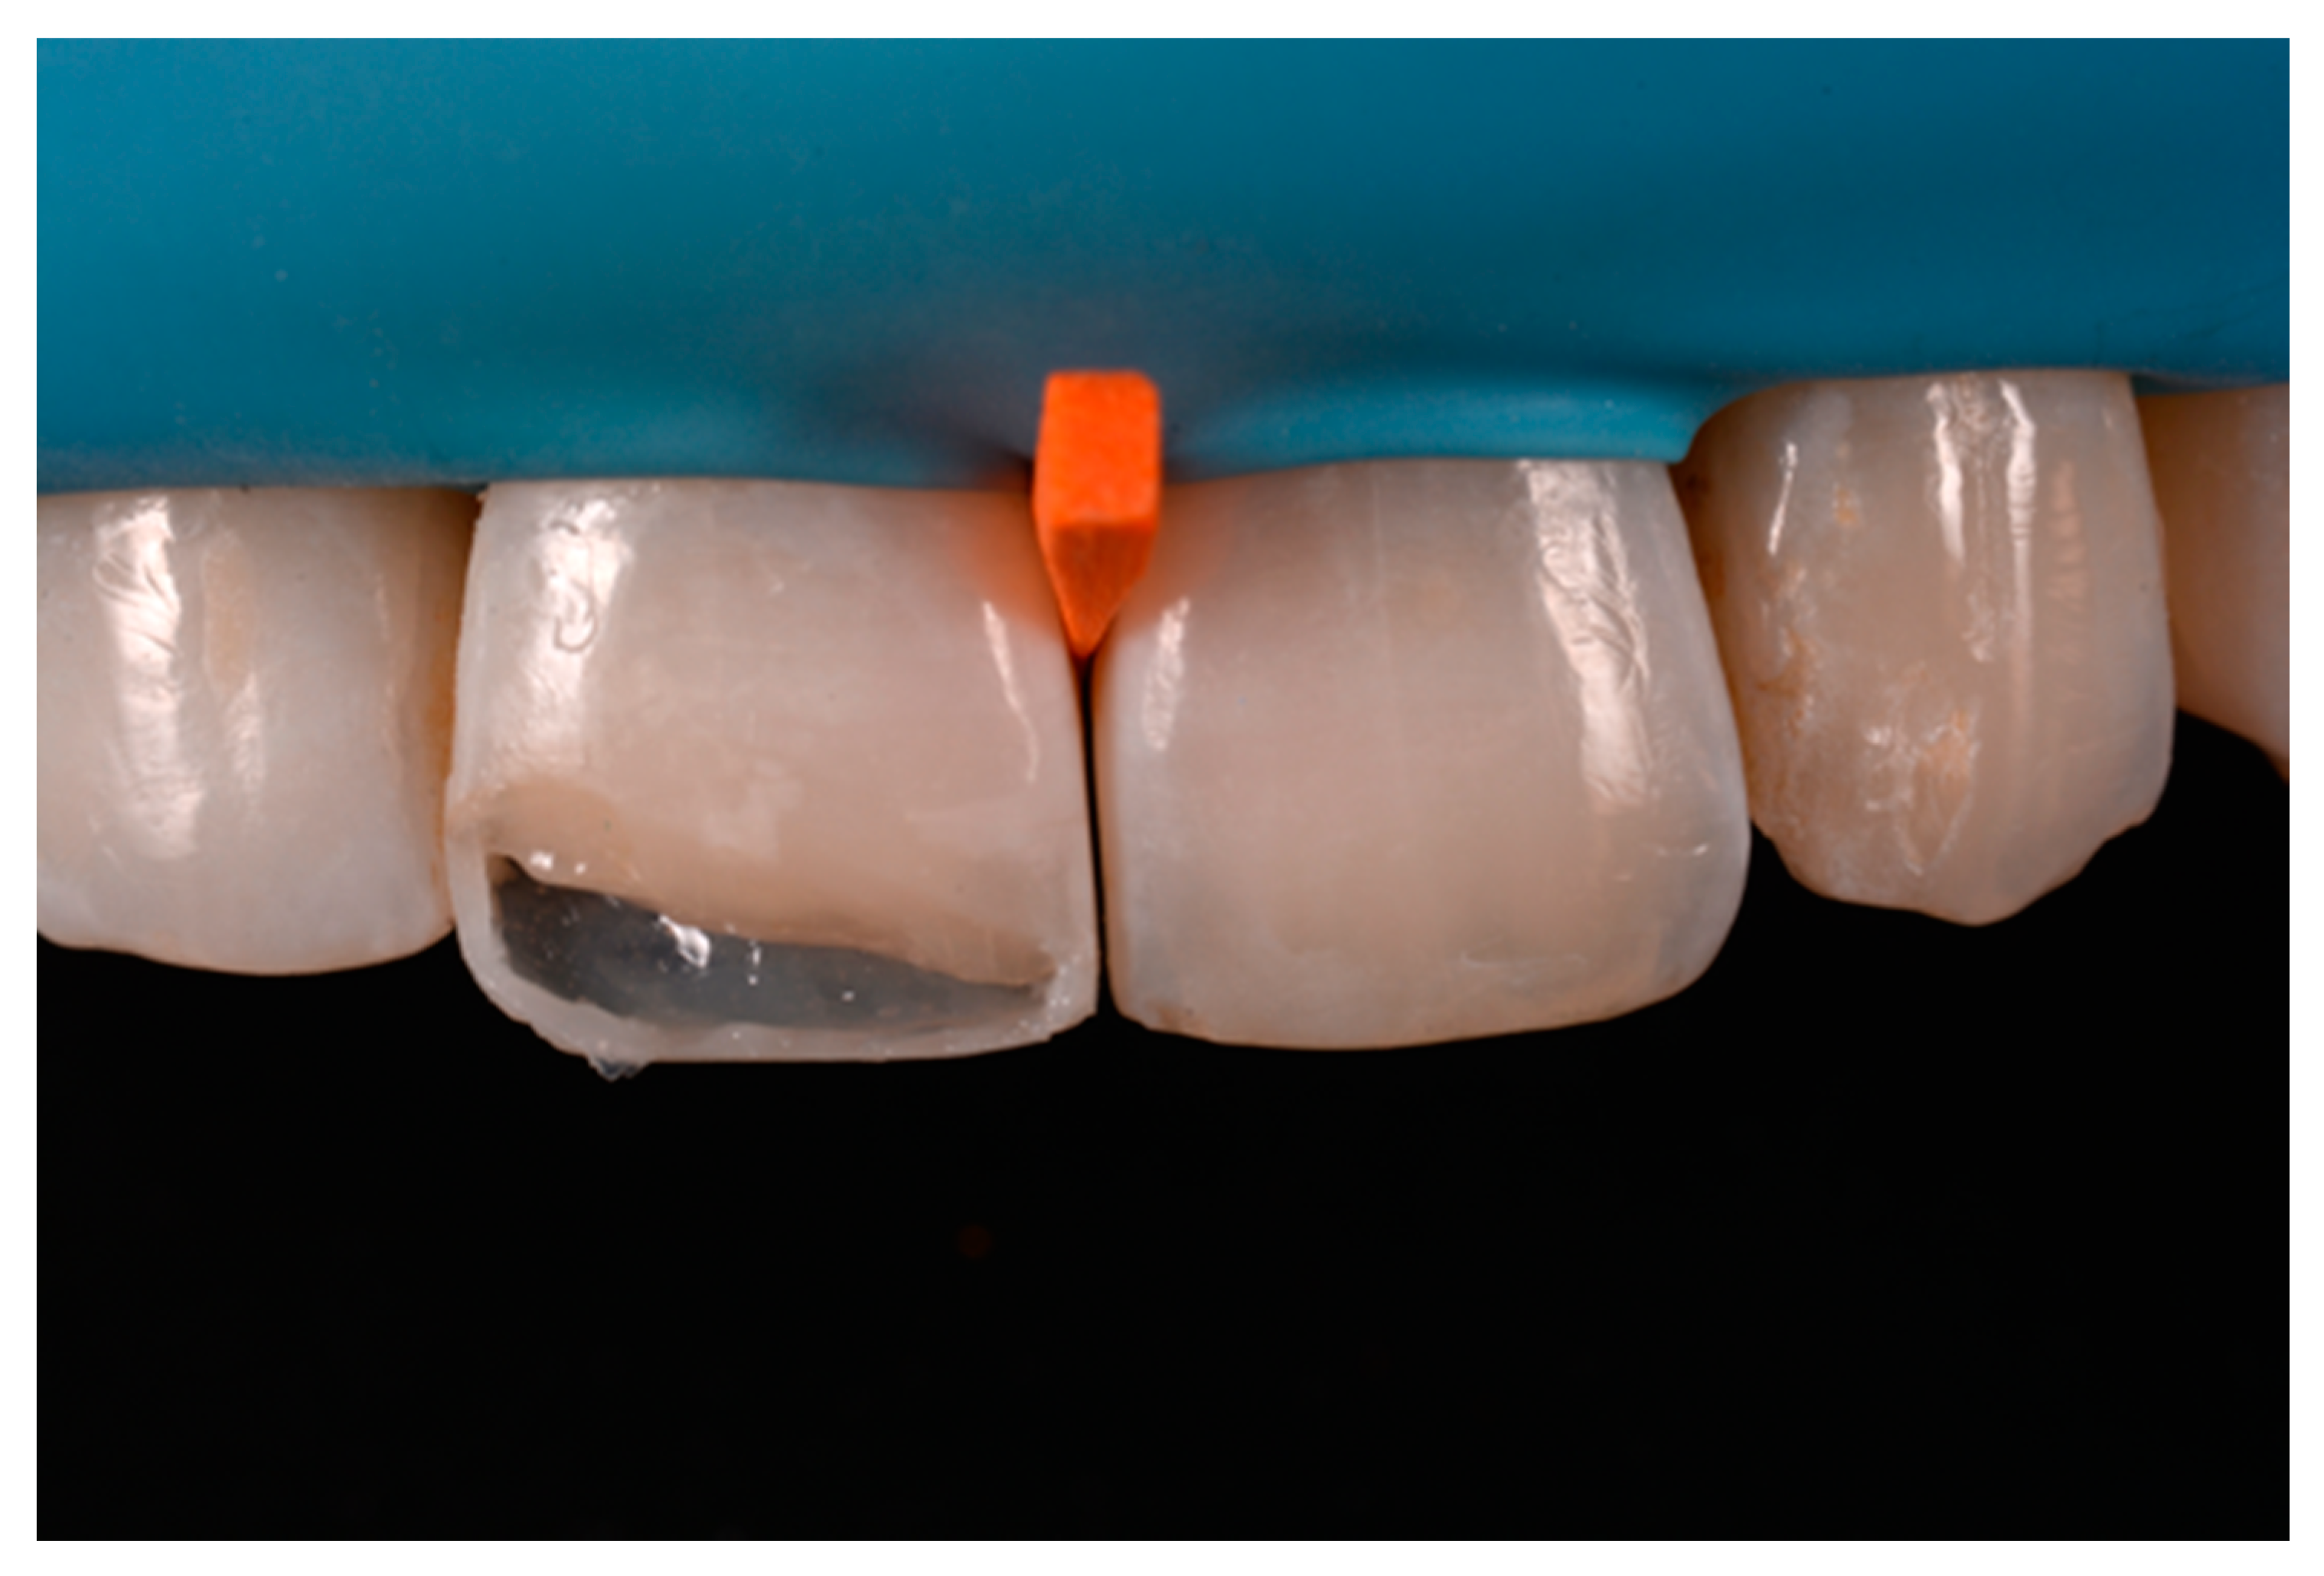

A 53-years old man presented to the dental office asking for the restoration of the mesial incisal angles of both central incisors (Figure 40). After preliminary shade analysis (using the button-try technique [14]) an attentive management of opaque and translucent shades was required to esthetically solve this case. After isolation with rubber dam, preparation, and adhesive procedures (Optibond FL, Kerr, Bioggio, Switzerland) the frame was completed using a translucent shade (Mosaic, ET, Ultradent Products, South Jordan, UT, USA) for palatal wall and an opaque material (Mosaic, A2, Ultradent Products, South Jordan, UT, USA) for incisal margin and interproximal walls. The external and internal excesses of the frame were modified (as described in Section 2.1.2) to obtain a uniform thin opaque outline as planned during the preliminary color/opacity analysis. This modification was performed to avoid the unfavorable uncovering of translucent areas during final finishing procedures that could result in an unaesthetic outcome. Once the definition of the external frame was completed, the mesial mamelon was modeled (Mosaic, A2, Ultradent Products, South Jordan, UT, USA) and the translucent material (Mosaic, ET, Ultradent Products, South Jordan, UT, USA) was applied. Finishing and polishing procedures (Jiffy, Ultradent Products, South Jordan, UT, USA) were completed afterwards.

A wise balance of these opaque and translucent shades represents the key factor in obtaining reliable esthetic outcomes and great attention should be paid for their correct positioning [10,27]. Nevertheless, it happens that, during the restorative procedures, some inaccuracies could be made resulting in having opaque shades in place of translucent ones. This is generally realized too late, after finishing and polishing procedures thus compromising the final esthetic result [25]. In Figure 58 in fact the esthetic outcome of the left central incisor could have been improved if the opaque incisal margin had been made thicker and festooned. Conversely, we can notice from Figure 59 excessive thickness in the opaque incisal margin that, if not reduced, could provide an unpleasant final esthetic result.

Figure 59.

Completing the restorations without previously reducing the incisal frame could provide an unpleasant final esthetic outcome.